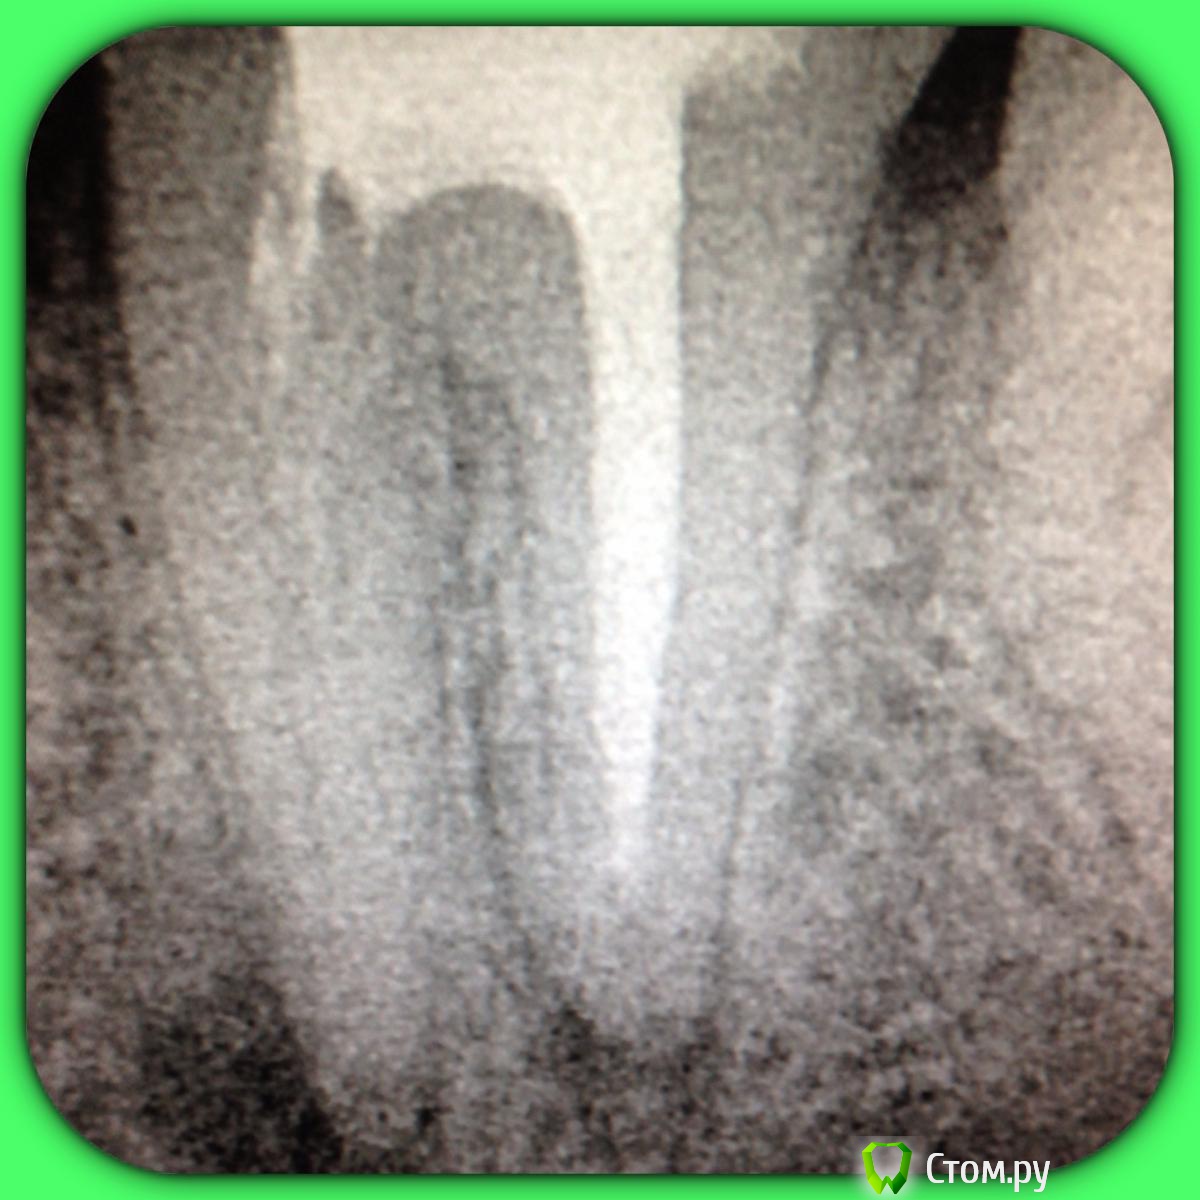

SSTi Опубликовано 13 июня, 2014 Автор Поделиться Опубликовано 13 июня, 2014 37. Медиальная стенка разрушена. Огромная старая пломба. Из жалоб только иногда болезненность по переходной. Редко. Очень. Делаю снимок. Коффер, преп, в дистальном какая-то паста плотная очень, светло-молочного цвета. В медиальный язычный без проблем попал. Щечный пришлось ковырять. Теперь о неприятном. Дистальный распломбировал, прошел, при этом раскрутил 3 протейпера и 1 профайл. В язычном медиальном проблем не было. А вот щечный- жутко узкий, прошел до куда смог. Раскрутил 3 протейпера, 2 профайла, 1 pathfile.... Дальше никак. До апекса еще миллиметров 5 точно. Хорошо хоть без поломок. Ручные к файлы гнулись только так. Даже десятка не идет. В общем очень хорошо помыл и кальций. Не знаю , что с щечным делать??? Биться дальше?? Сомневаюсь, что смогу. Это в процессе. Вот до куда дошел в щечном. С дистального потом убрал со стенок остатки материала Ссылка на комментарий

SSTi Опубликовано 13 июня, 2014 Автор Поделиться Опубликовано 13 июня, 2014 У язычного длина 23.5. В щечный файл заходит на 17-18мм. Надо будет развернуть трубку и сделать под углом в следующий раз. Апекс молчит как партизан в щечном. Ссылка на комментарий